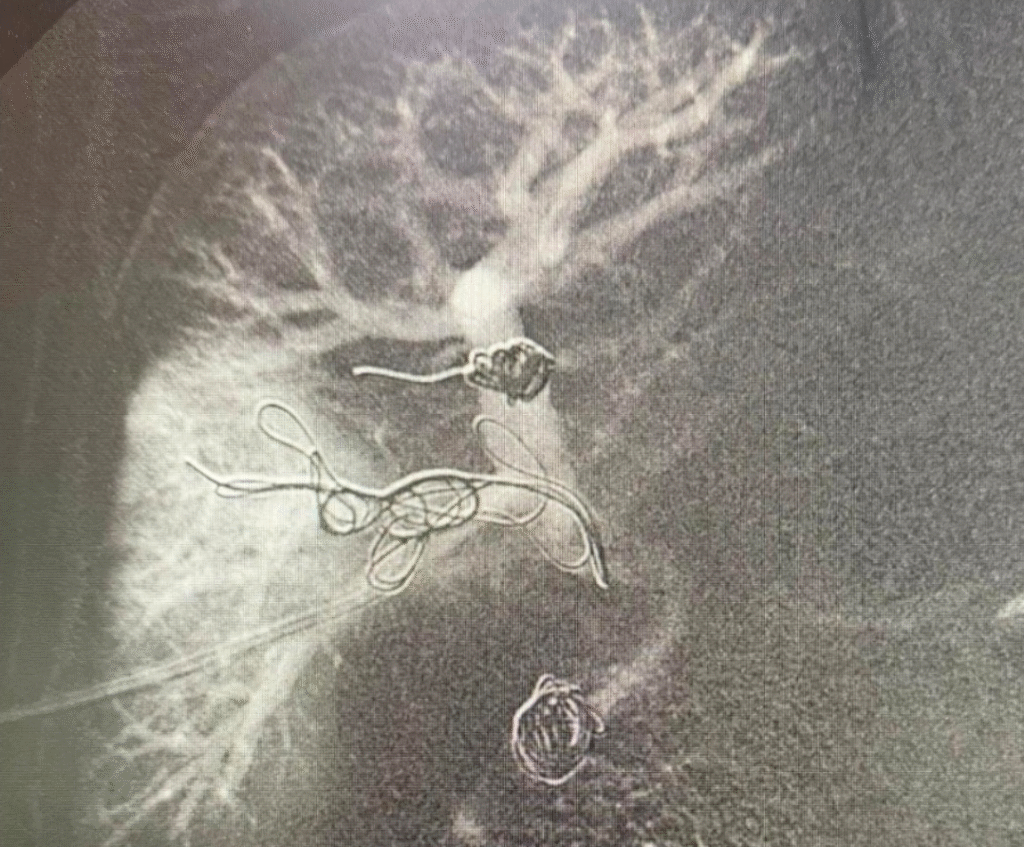

A intervenção foi conduzida pelos cirurgiões vasculares e endovasculares Romulo Bizare e Silfayner Dias e consistiu na realização da embolização da veia porta, a principal veia do fígado.

Isso, por meio de punção trans-hepatica percutânea guiada por ultrassom, técnica considerada de alta complexidade.